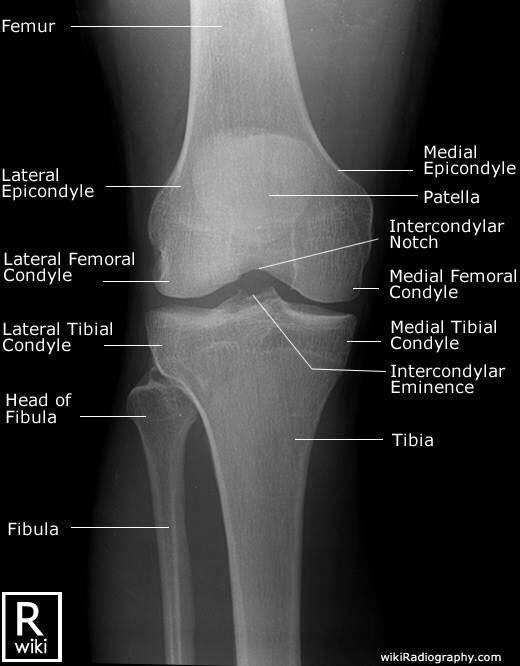

Las radiografías, generalmente llamadas rayos X, producen imágenes como sombras de huesos y ciertos órganos y tejidos. Las radiografías son muy buenas para detectar problemas óseos. Pueden mostrar algunos órganos y tejidos blandos; sin embargo, la MRI y la CT suelen crear mejores imágenes de los mismos. Aun así, las radiografías son rápidas, fáciles de obtener y menos costosas que los otros estudios, por lo que se pueden usar para obtener información rápidamente.

Un tubo especial dentro de la máquina de rayos X emite un haz de radiación controlada. Los tejidos del cuerpo absorben o bloquean la radiación en diferentes grados. Los tejidos densos como los huesos bloquean la mayor parte de la radiación, pero los tejidos blandos, como la grasa o los músculos, bloquean menos radiación. Después de pasar por el cuerpo, el haz alcanza una pieza de un fragmento de película o un detector especial. Los tejidos que bloquean altas cantidades de radiación, como los huesos, aparecen como áreas blancas en un fondo negro. Los tejidos blandos bloquean menos radiación y aparecen en tonos de gris. Los órganos que contienen principalmente aire (como los pulmones) aparecen en negro. Los tumores son por lo general más densos que el tejido que los rodea, por lo que suelen verse en tonos grises más claros.